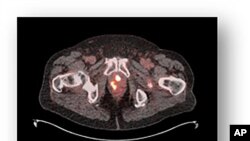

ARCHIVO -Imagen de una próstata con signos de cáncer. Los hombres latinos enfrentan tasas elevadas de cáncer de próstata en Estados Unidos, siendo la cuarta causa de muerte por cáncer en esta población.

El cáncer de próstata es el más diagnosticado entre hombres latinos en EEUU, con 13.000 casos anuales. Barreras culturales, económicas y de acceso al sistema de salud dificultan su detección temprana y tratamiento, acentuando disparidades entre latinos según su origen y lugar de nacimiento.

El cáncer de próstata es una de las enfermedades más comunes entre los hombres en Estados Unidos y la principal causa de diagnóstico de cáncer entre los hombres latinos.

Según el estudio Avanzando la Ciencia del Cáncer en los Latinos de Mariana Stern, recopilado en la Biblioteca Nacional de Medicina de los Institutos Nacionales de Salud de Estados Unidos (NIH, en inglés), cada año se detectan más de 13.000 nuevos casos de esta enfermedad en latinos, y aproximadamente 1.800 de ellos pierden la vida debido a complicaciones asociadas.

Estas cifras posicionan al cáncer de próstata como la cuarta causa de muerte por cáncer en esta comunidad.